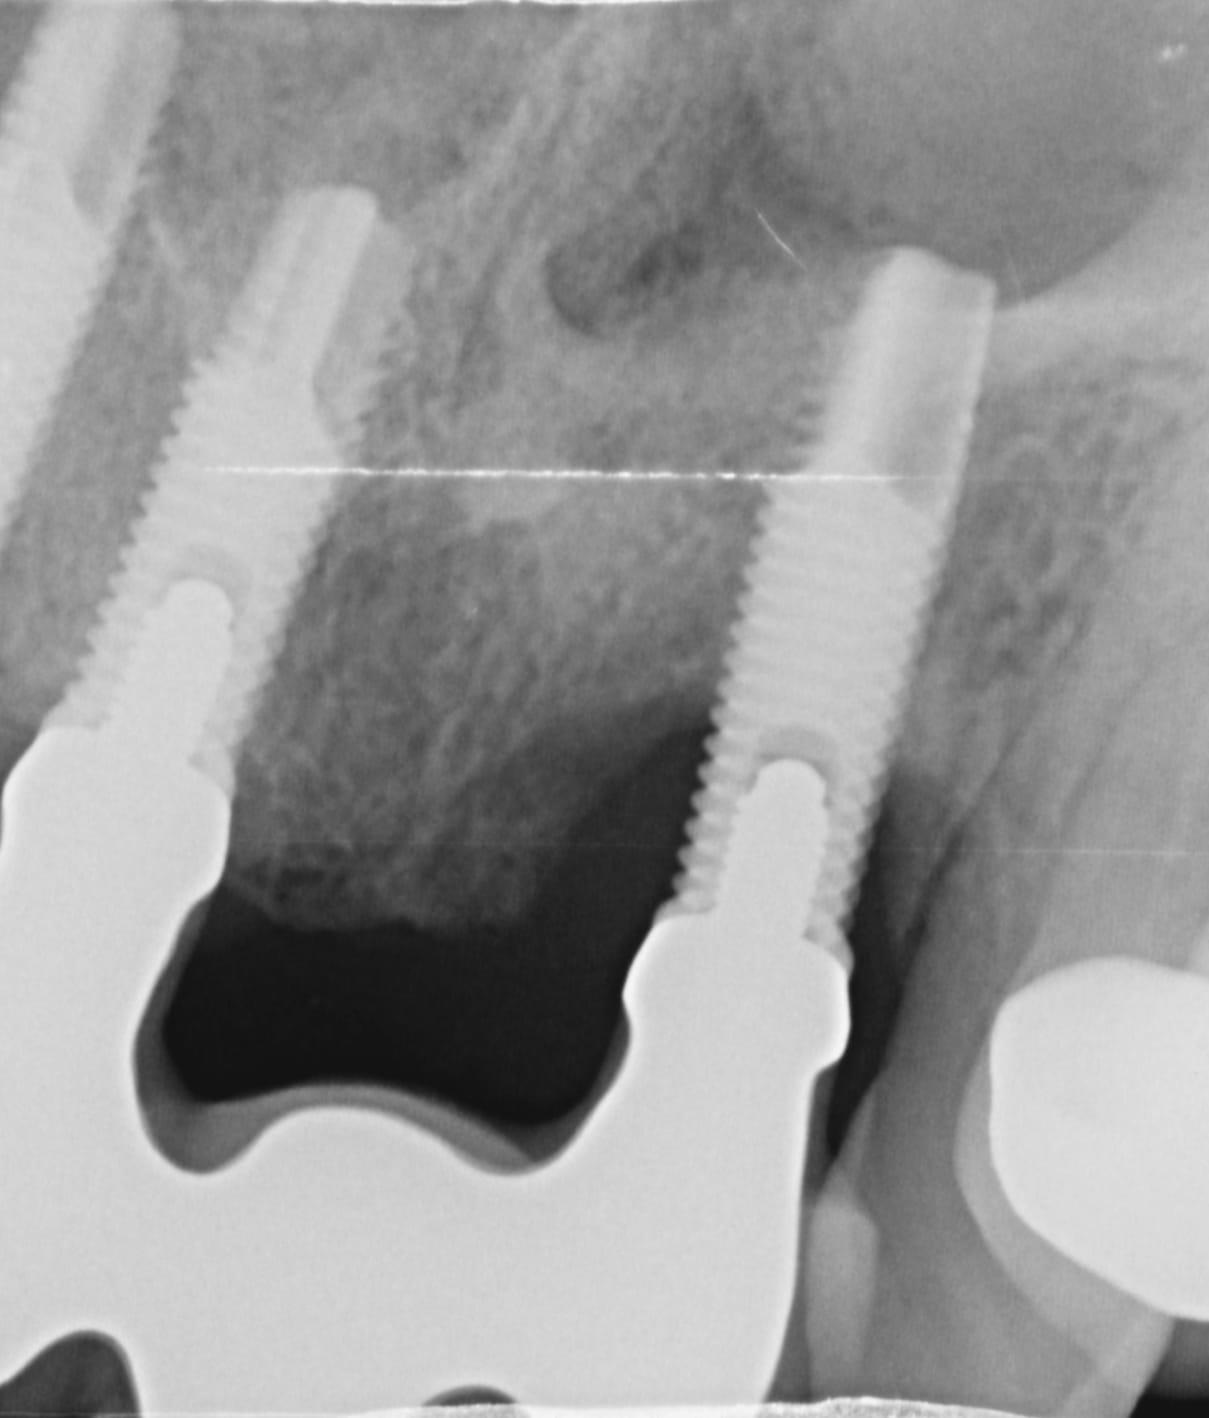

Laser Assisted Treatment of Peri-implantitis

There is no long term data on the treatment of peri-implantitis. The application of the laser for this use is relatively recent. However, the case results are superior to our conventional treatment. The risk to the implant and the patient is low, cost is low and treatment is also minimally invasive.